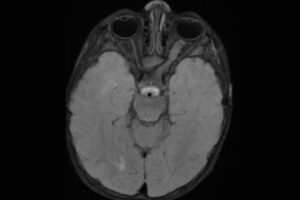

Nearly all adults with Down syndrome will develop evidence of Alzheimer’s disease by late middle age. A new study by researchers at Washington University School of Medicine in St. Louis shows that the disease both starts earlier and moves faster in people with Down syndrome, a finding that may have important implications for the treatment […]

Alzheimer’s disease progresses faster in people with Down syndrome (Links to an external site)